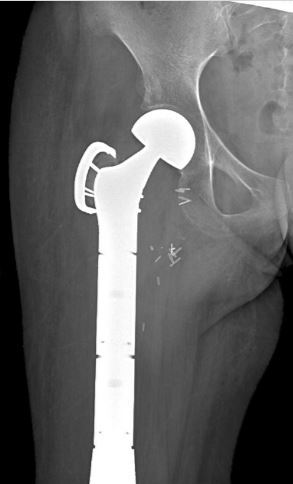

Xray of Prosthesis

This is an x-ray of a patient after the surgical placement of the prosthesis and removal of upper femur.